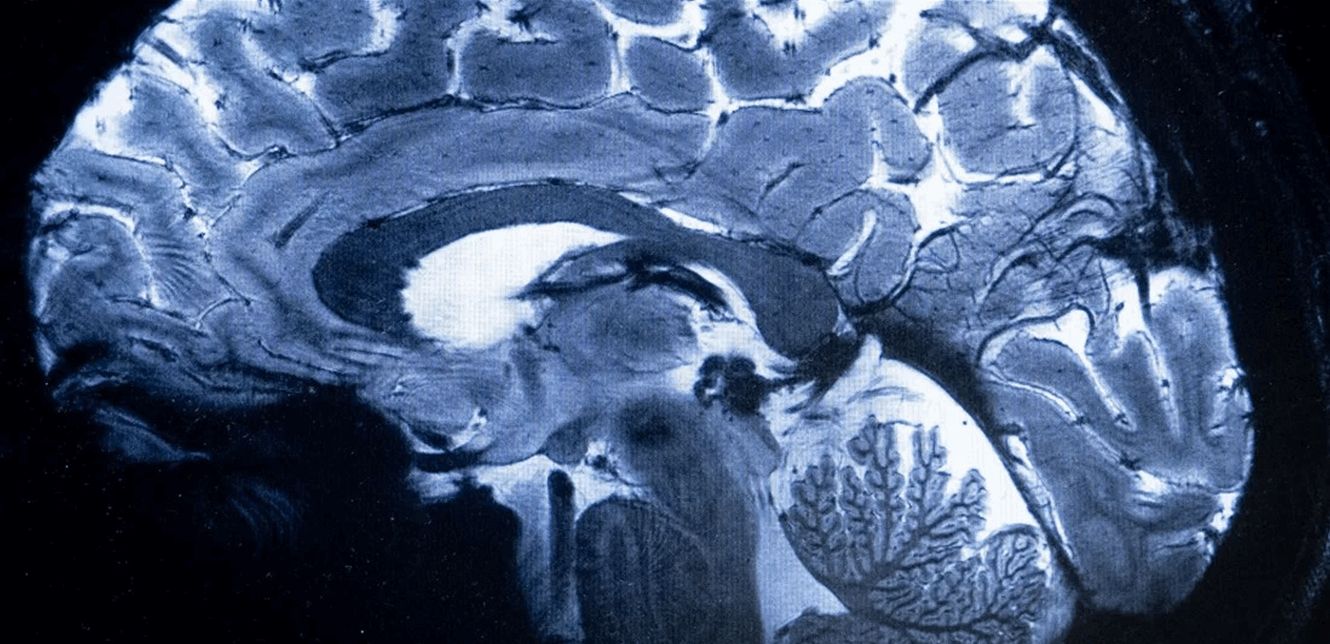

وأظهرت عمليات مسح التصوير بالرنين المغناطيسي لـ30 مريضا أدخلوا المستشفى بسبب "كوفيد 19" في وقت مبكر من الوباء قبل نشر اللقاحات، علامات على التهاب في جذع الدماغ، وهو جزء صغير لكنه بالغ الأهمية لأنه يتحكم بوظائف الجسم التي تدعم الحياة، مثل التنفس والنبض وحركة الدم.

واستخدمت روا وزملاؤها أجهزة تصوير بالرنين المغناطيسي قوية لفحص أدمغة المرضى، وكشفت هذه الأجهزة عن تفاصيل كافية لرؤية الالتهابات والتشوهات الدقيقة في أنسجة جذع الدماغ، علما أن جميع المرضى أدخلوا إلى المستشفى بسبب إصابات شديدة بفيروس كورونا قرب بداية الوباء.